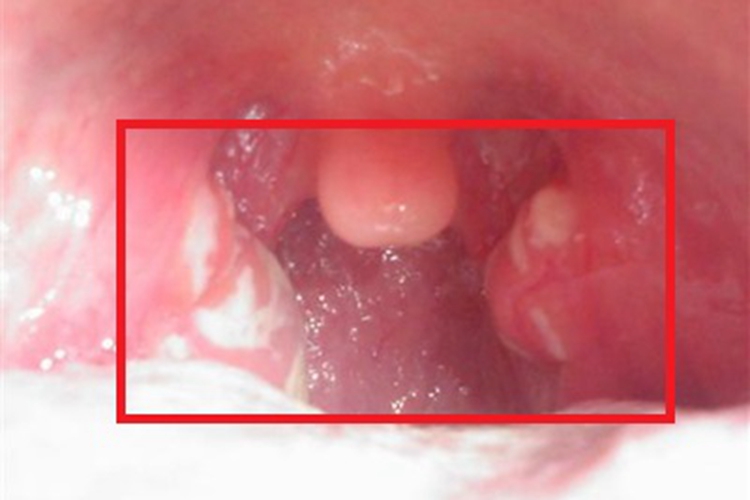

慢性鼻咽炎累及咽后壁时,表现为局部黏膜有不同程度的充血、红肿,可高于周围黏膜,表面有黄白色脓性稠厚状分泌物覆盖,伴有鼻咽干燥感、声嘶及头痛等不适。